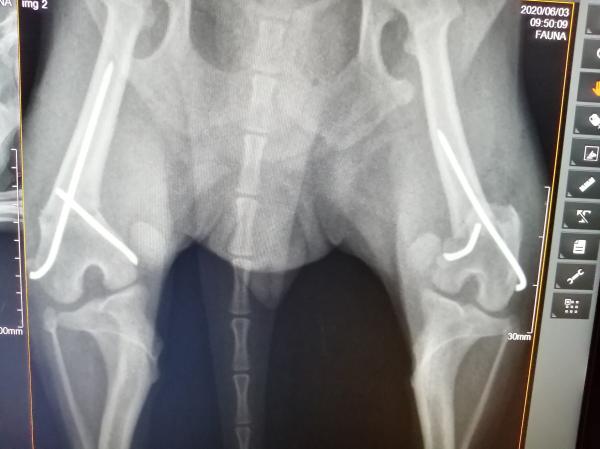

El 27 de mayo cirugía, está radiografía de hoy y se ve cómo está su pata izquierda, le hacen cirugía de corrección y comenta el doctor que le dejó tal cual cuál su fémur solo le apretó los clavos porque ya solo el HUESO mi pregunta es

El miércoles 37 de junio del 2020 operaron a mi chihuahueña de 3 años tuvo politraumatismo en las patas traseras en la altura del fémur cerca de la rodilla le pusieron dos clavos cruzados en cada pata, pero hoy miércoles 8 días después se le hizo una cirugía de corrección de la pata izquierda, porque su fractura quedó igual como si no se le hubiera hecho nada , el médico dijo que sólo le volvió a colocar los clavos más apretados porque su fractura ya estaba soldada vy ya no podía hacer nada, mi pregunta es ES POSIBLE QUE LA FRACTURA YA HAYA SOLDADO EN 8 DIAS Y NO SE PUEDA CORREGIR?, la perrita tiene 4 años 6 meses